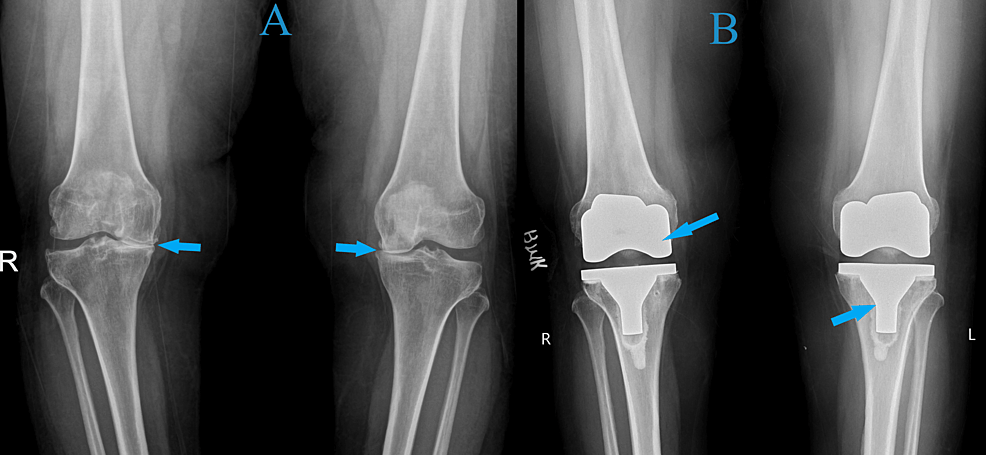

- Radiografia oferă imagini detaliate ale oaselor și poate evidenția îngustarea spațiului articular, modificări osoase și osteofite.

- Osteotomie: realinierea femurului sau tibiei pentru a redistribui greutatea

- Proteza totală sau parțială de genunchi: înlocuirea suprafețelor articulare deteriorate

Recuperare